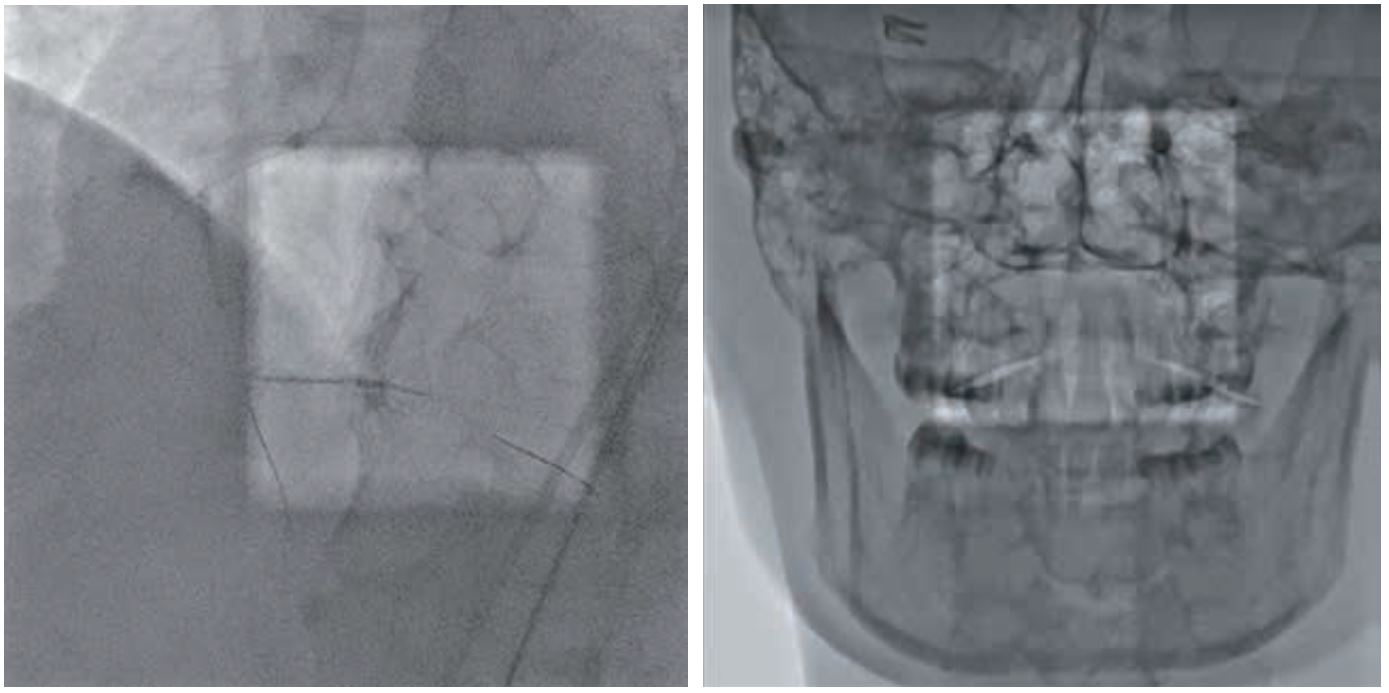

• Позиціонування системи під оптимальним кутом із неперевершеним анатомічним покриттям – від голови до ніг пацієнта і від пальця однієї його руки до пальця іншої

• Відтворення прямого зображення на екрані незалежно від кута повороту детектора завдяки синхронізованому обертанню детектора та коліматора

• Вільний простір навколо голови пацієнта забезпечує безперешкодний доступ до нього персоналу та додатковому обладнанню

• Режим Spot Fluoro передбачає асиметричну, сфокусовану на проблемній ділянці колімацію з одночасним відображенням оточуючої області та збереженням дози до 70%.

• Режим SPOT ROI допомагає зменшити дозу поза межами області інтересу, одночасно дозволяючи візуалізувати навколишню анатомію завдяки застосуванню спеціального фільтру. Відображення не лише пристрою, а й навколишньої анатомії під час встановленняпристрою є дуже важливим для успішного результату.